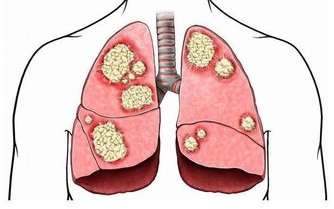

1、肺痛累及胸痛、肩背痛。當了肺癌晚期後,疼痛可以說是每個患者都會出現的症狀。大多數已發生胸內區域性播散的肺癌患者均有胸痛的症狀。肺外圍型肺癌常向後上發展,侵蝕胸膜,累及肋骨和胸壁組織,從而引起肩背痛。這類患者很少有呼吸道症狀。